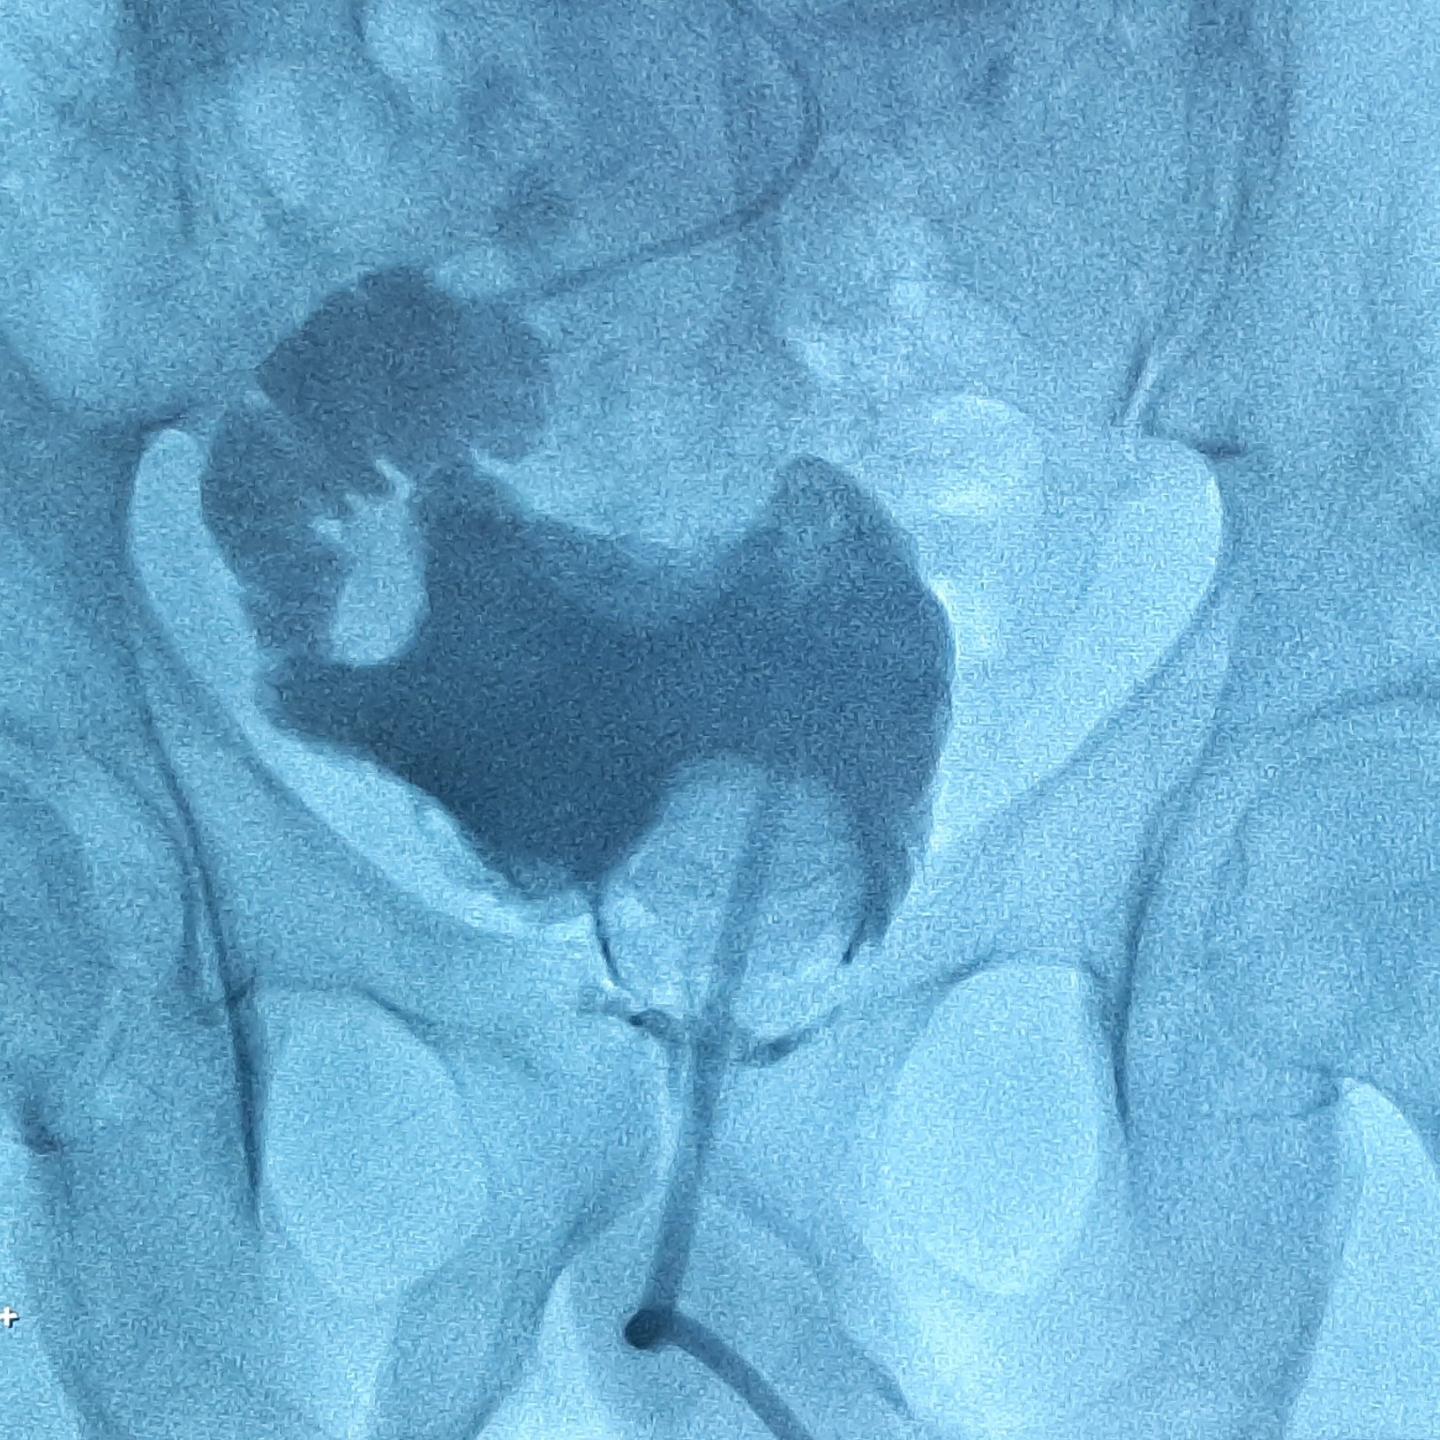

Bij mij zijn met toeval ( zonder klachten of bloed in de urine) in 2018 in de blaas/wand tumor plekjes ontdekt met camera en later bevestigd met biopten.

Na bijna 3 jaar blaasspoelingen en bijna klaar kreeg ik de mededeling dat de tumor de blaas uit was gegroeid.